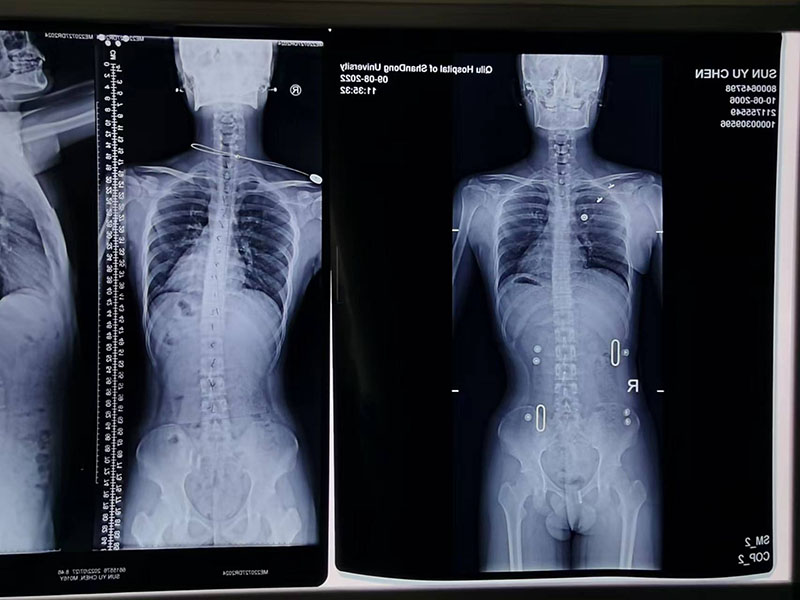

脊柱侧弯矫形器

康复实例